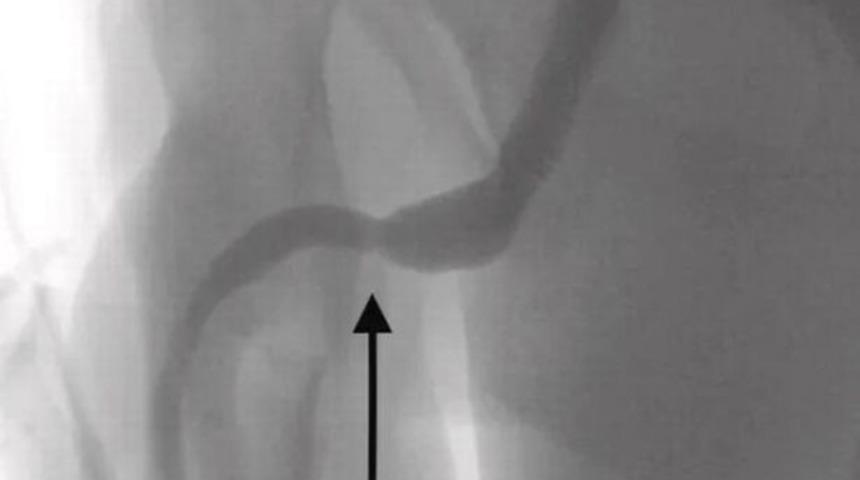

Doktorlar raporda, “USB kablosunun iki distal portunun dış üretral kanaldan dışarı çıktığı ve düğümlü telin orta kısmının üretra içinde kaldığı tespit edildi. Hasta, ruh sağlığı bozukluğu öyküsü olmayan sağlıklı bir ergendi. Palpabl yabancı cisim üzerinde uzunlamasına bir penoskrotal insizyon yapıldı ve daha derin dokularda dikkatli bir diseksiyon yapıldı ve bulbospongiosus kasını ayırdı. Telin her iki ucu da dış üretral kanaldan başarıyla çıkarıldı." ifadelerine yer verildi.

Doktorlar metal bir çubuk kullanarak USB kablosunu çıkartmak için girişimde bulundu ancak kablonun düğümlenmesi bu yöntemi imkansız hale getirdi. Doktorlar kabloya ulaşmak için cinsel organ ile anüs arasındaki bölümü kesmek zorunda kaldılar. Tıbbi yöntemin sonrasında söz konusu raporda, “Cinsel deneyim ve doyumun yanı sıra altta yatan zihinsel bozukluklar, üretra ve mesanede tutulan yabancı cisimlerin ana nedenleri olarak kabul edilir. Yönetim, nesnenin şekline ve boyutuna ve yerleştirme mekanizmasına bağlı olarak değişir.